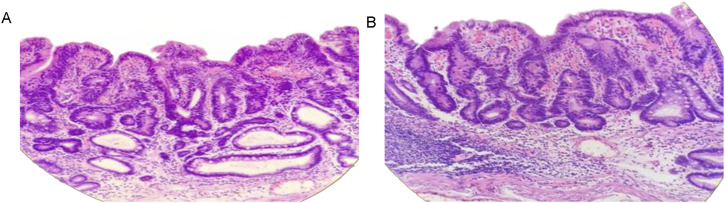

Background: "Crawling-type" early gastric carcinoma (EGC) is a rare subtype of gastric cancer (GC) that is challenging to diagnose at an early stage due to its low-grade nuclear heterogeneity and morphology that mimics intestinal metaplasia. This study aimed to explore the clinical characteristics and pathological features of patients with crawling-type EGC.

Results: 8 patients (mean age 63.5 ± 7.8 years) were included: 4 underwent ESD, and 4 underwent partial gastrectomy. In 4 patients, the tumors were primarily located in the gastric cardia and the basal gland area of the upper stomach, while the other 4 patients had tumors in the antral region. Preoperative gastroscopy revealed atrophic gastritis and intestinal metaplasia in all patients. The lesions were generally flat in morphology. Submucosal infiltration was found in only one case. Signet ring cells were present in the tumors of 5 patients. The mucinous type was observed in 7 patients. Seven tumors were of the gastrointestinal mixed type. Curative resection was achieved in all patients. No recurrence events were observed in any patient at 1 year after surgery.

Conclusions: The crawling-type EGC may exhibit distinct clinical characteristics and pathological features compared with classical GC. Curative resection was achieved in all patients. The short-term prognosis of surgical treatment may be favorable.